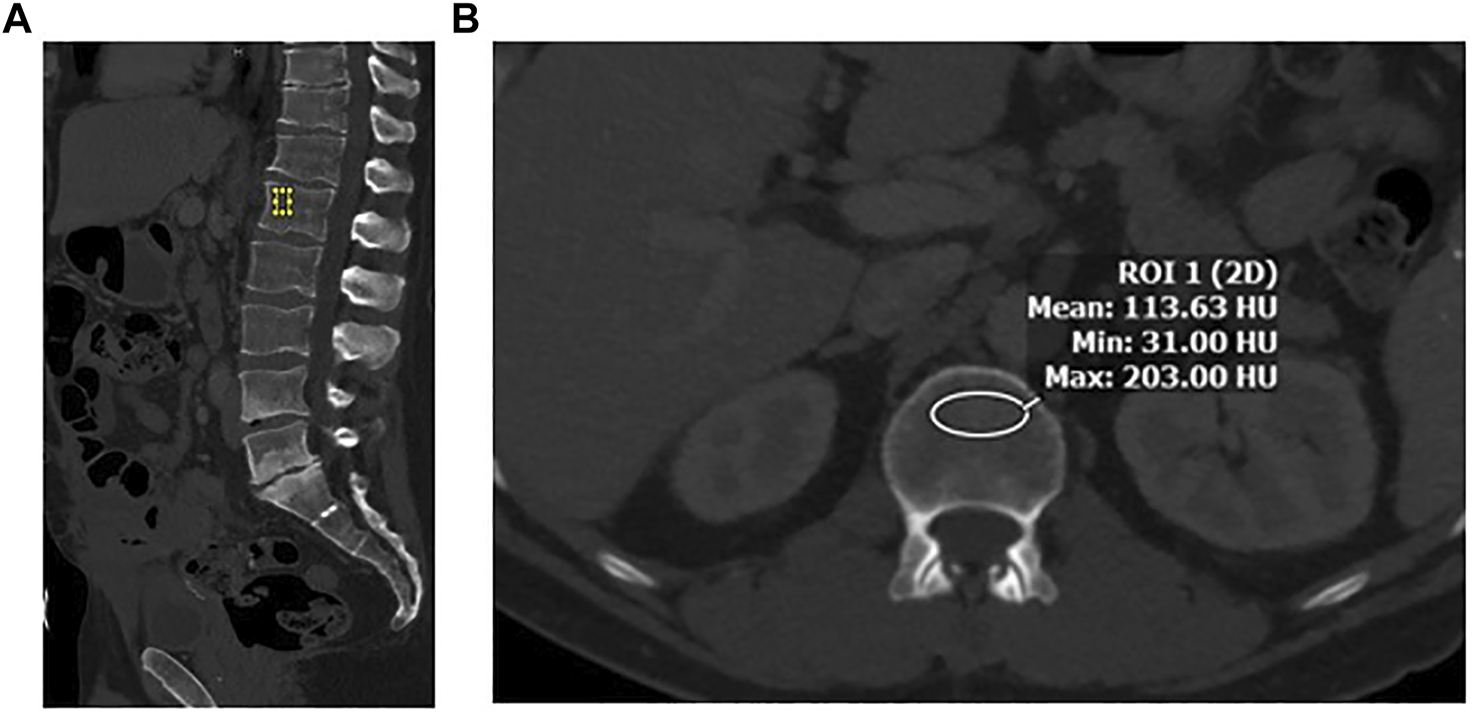

A region of interest (ROI) was drawn manually at the L1 vertebral body. It is the first non–rib-bearing vertebra and can be seen on both abdominal and thoracic CT scans. The L1 vertebra avoids most degenerative processes, and HU thresholds have been determined for L1 with excellent interobserver agreement. The HU value was determined by drawing an ellipse as large as possible on the axial and the midsagittal reconstruction in the anterior two-thirds of the vertebral body (Figure 1). This avoids venous channels in the posterior vertebra and should only include the trabecular bone. Additional images were assessed for occult vertebral fracture. The average of the mean HU values from the ROIs was recorded. Care was taken to note the model and voltage of the CT image and standardization of images and reviewed by a single abdominal radiologist (ZS).

FIGURE 1

(A) Sagittal image in bone windows demonstrating placement of an elliptical region of interest at L1 along the anterior aspect of the vertebral body. (B) Axial image at the L1 level along the superior aspect, with an elliptical region of interest to measure CT-derived bone density in Hounsfield Units (HU).